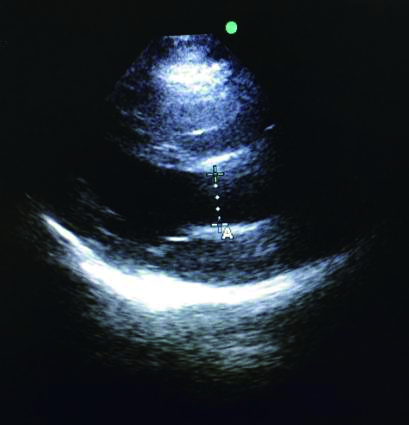

充分暴露前胸部,于胸骨旁长轴切面,选取主动脉瓣根部测量左室流出道直径与截面积。选取心尖五腔心切面,通过脉冲多普勒测量动脉流速,计算左心室流出道收缩高峰期的流速时间指数,测量心率,最后通过心脏检查软件包自动计算出CO(图 3、4)。通过上述PLR试验,联合超声获得的CO,最后计算ΔCO值,ΔCO≥15%定义为容量反应性阳性;反之为容量反应性阴性。

| 图 3 胸骨旁长轴主动脉根部 Figure 3 The aortic root at parasternal long axis |